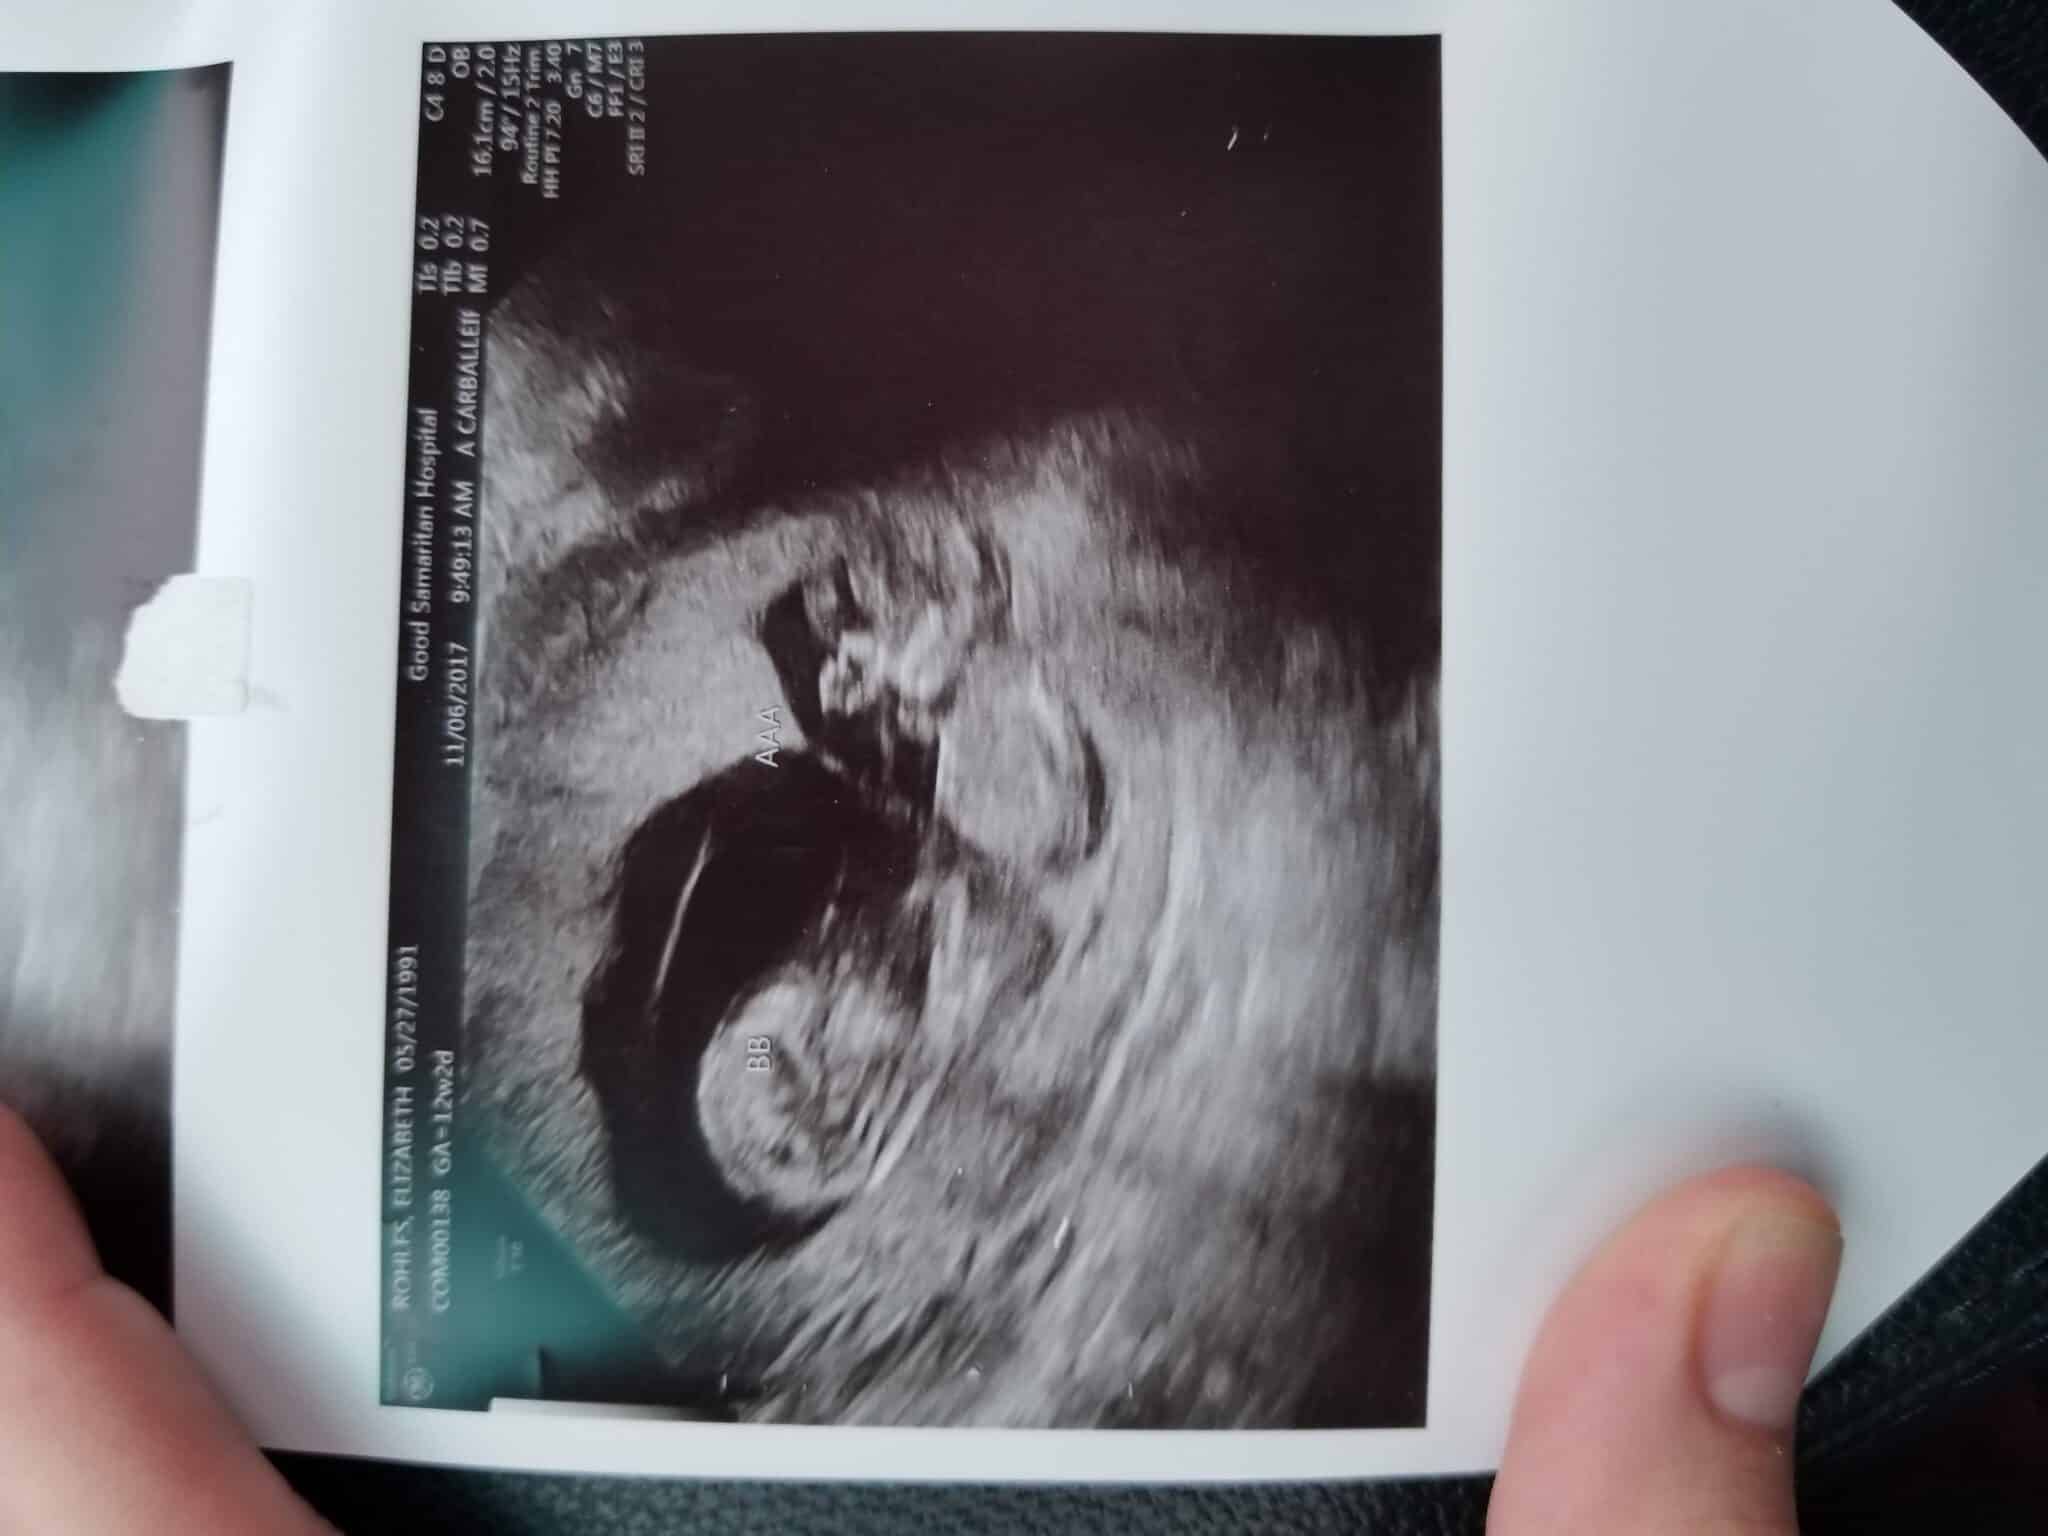

Ultrasound Photos at 12 Weeks Pregnant With Twins